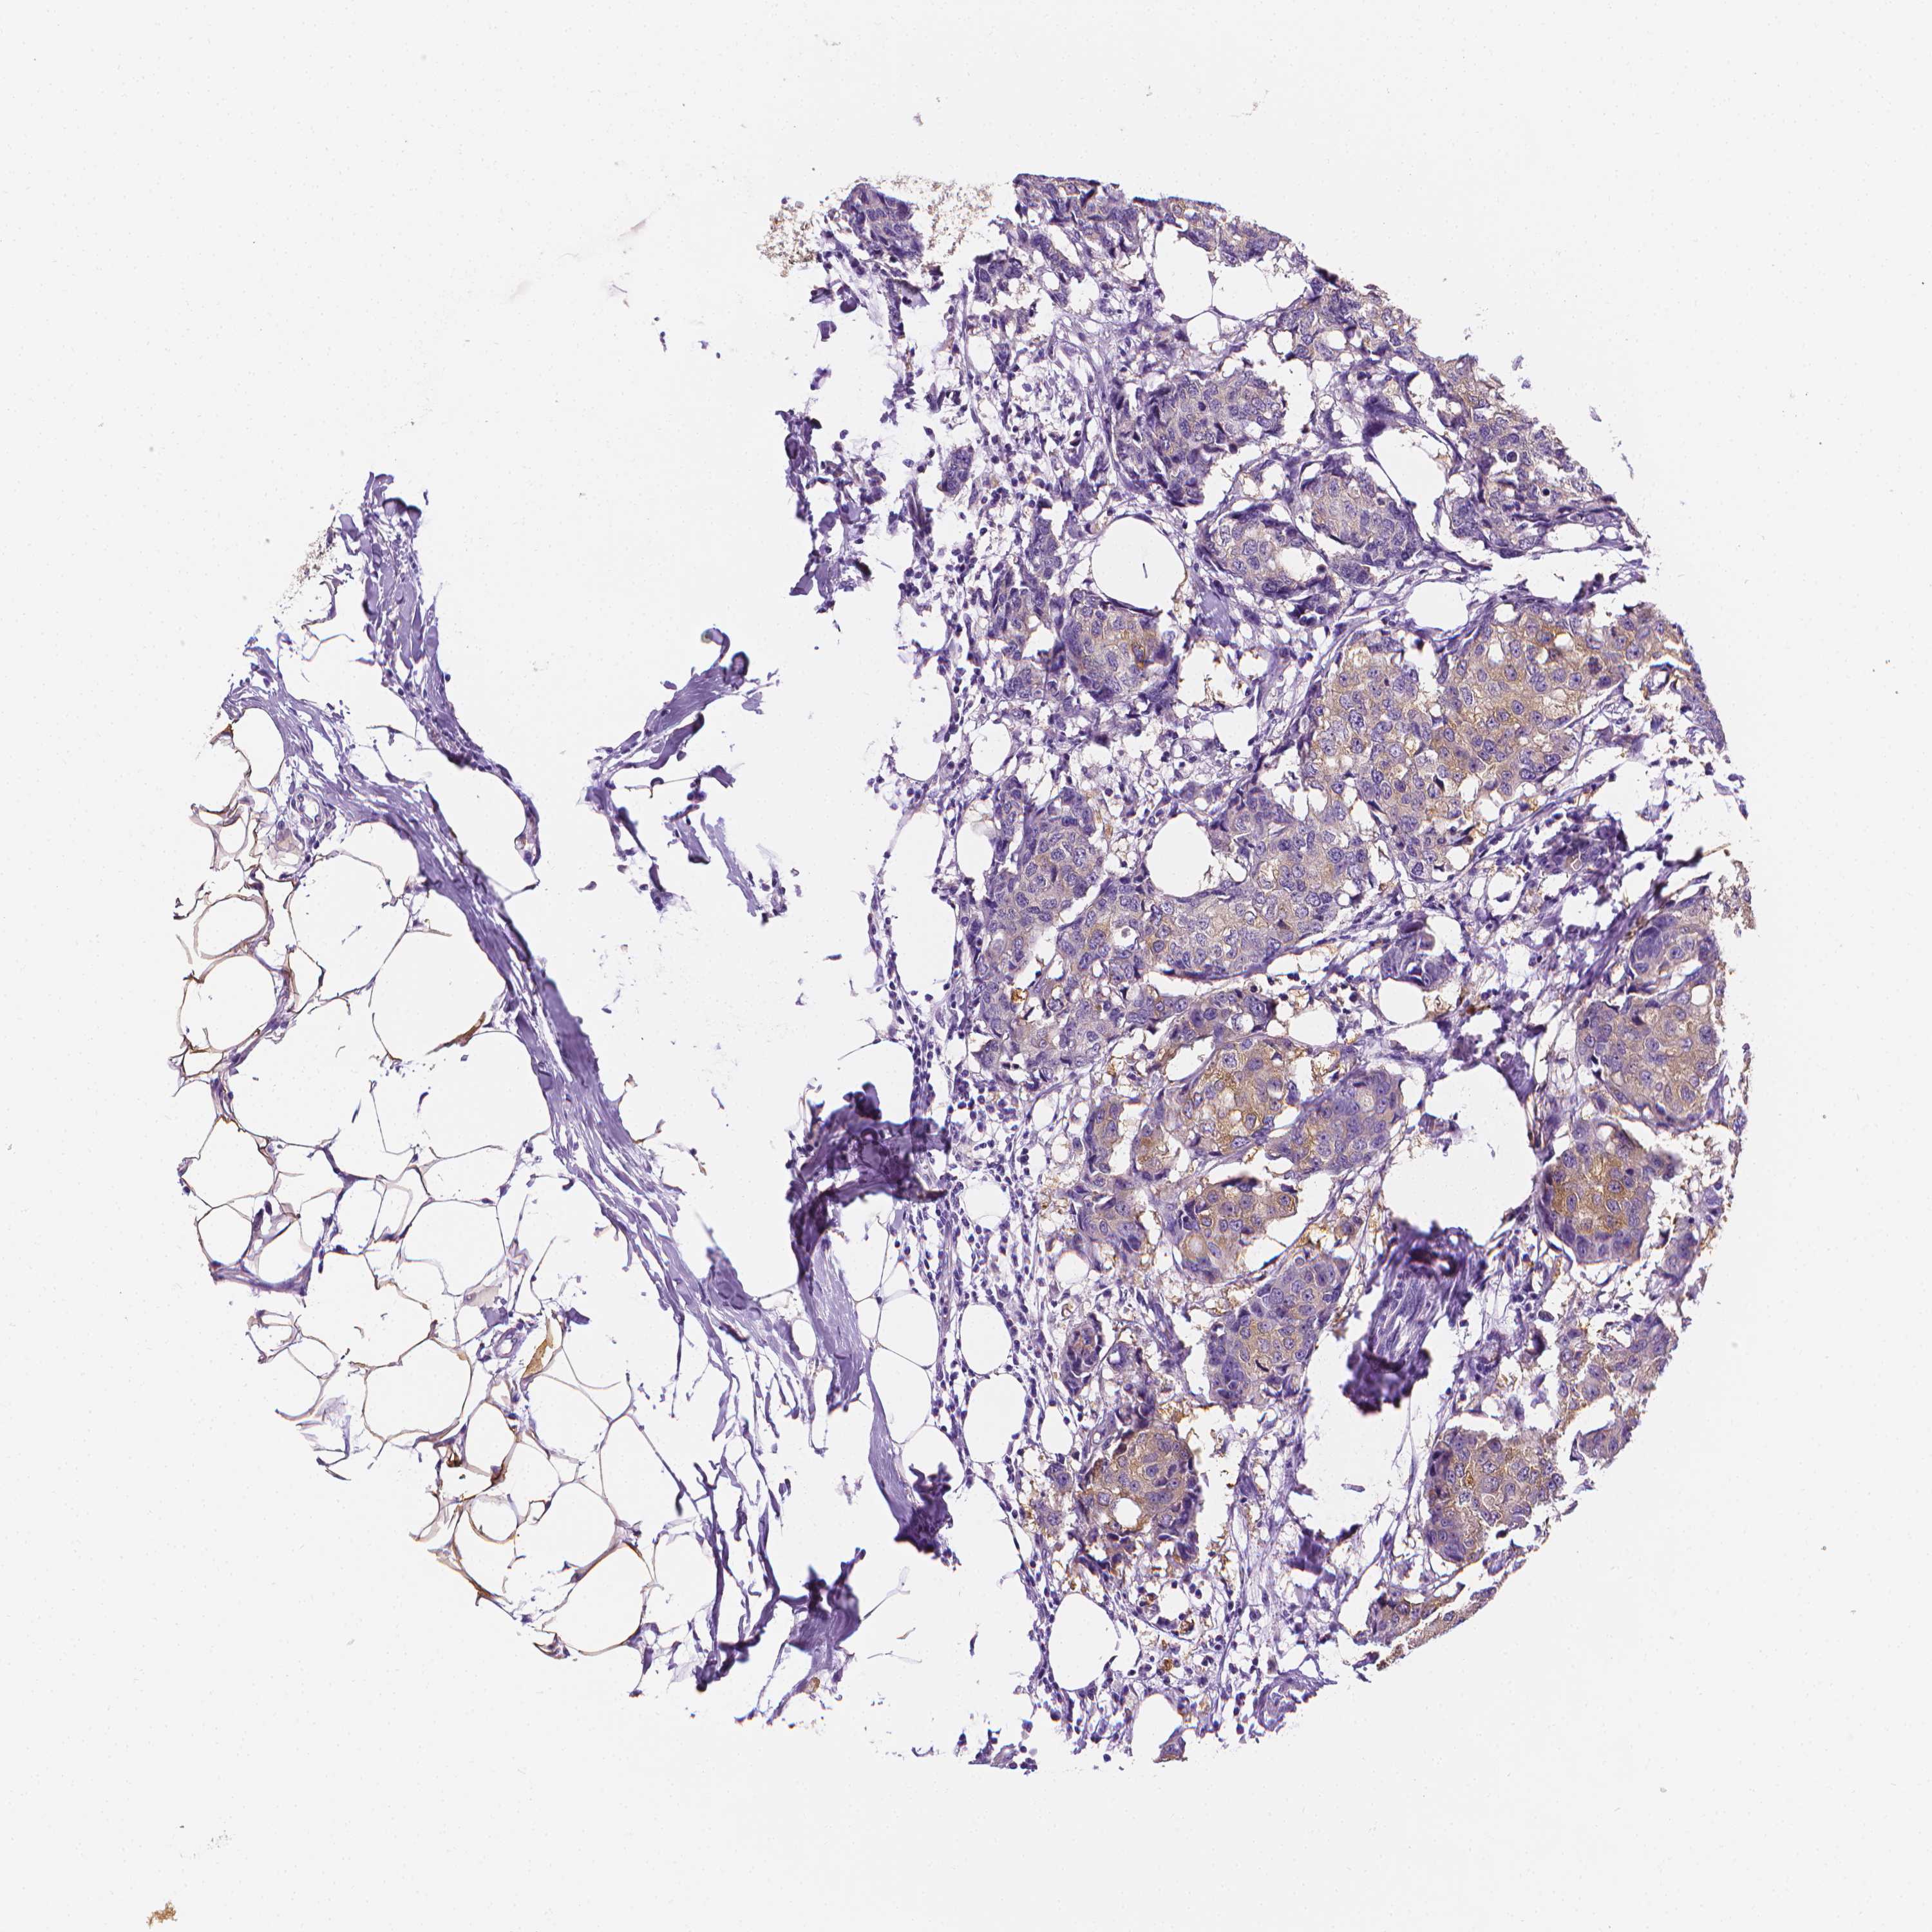

CANCER BREAST CANCER Show tissue menu

BRCA TCGA BRCA VALIDATION PROTEIN EXPRESSION